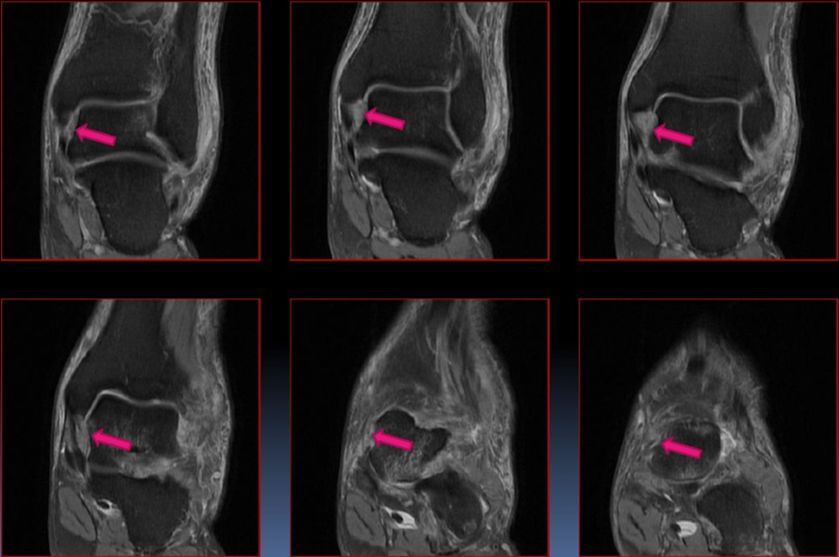

五、三角骨综合症

三角骨是距骨后端二次化中心,由软骨桥相连接。

病因:距骨三角骨急性骨折或慢性应力性骨折,胫骨后部或附近肌腱韧带反复撞击、压迫三角骨,引起踝关节囊后部级相邻的韧带和拇长屈肌腱的炎症。

MRI显示三角骨内骨髓水肿,邻近关节囊积液,软组织水肿级炎症,拇长屈肌腱水肿、腱鞘积液。